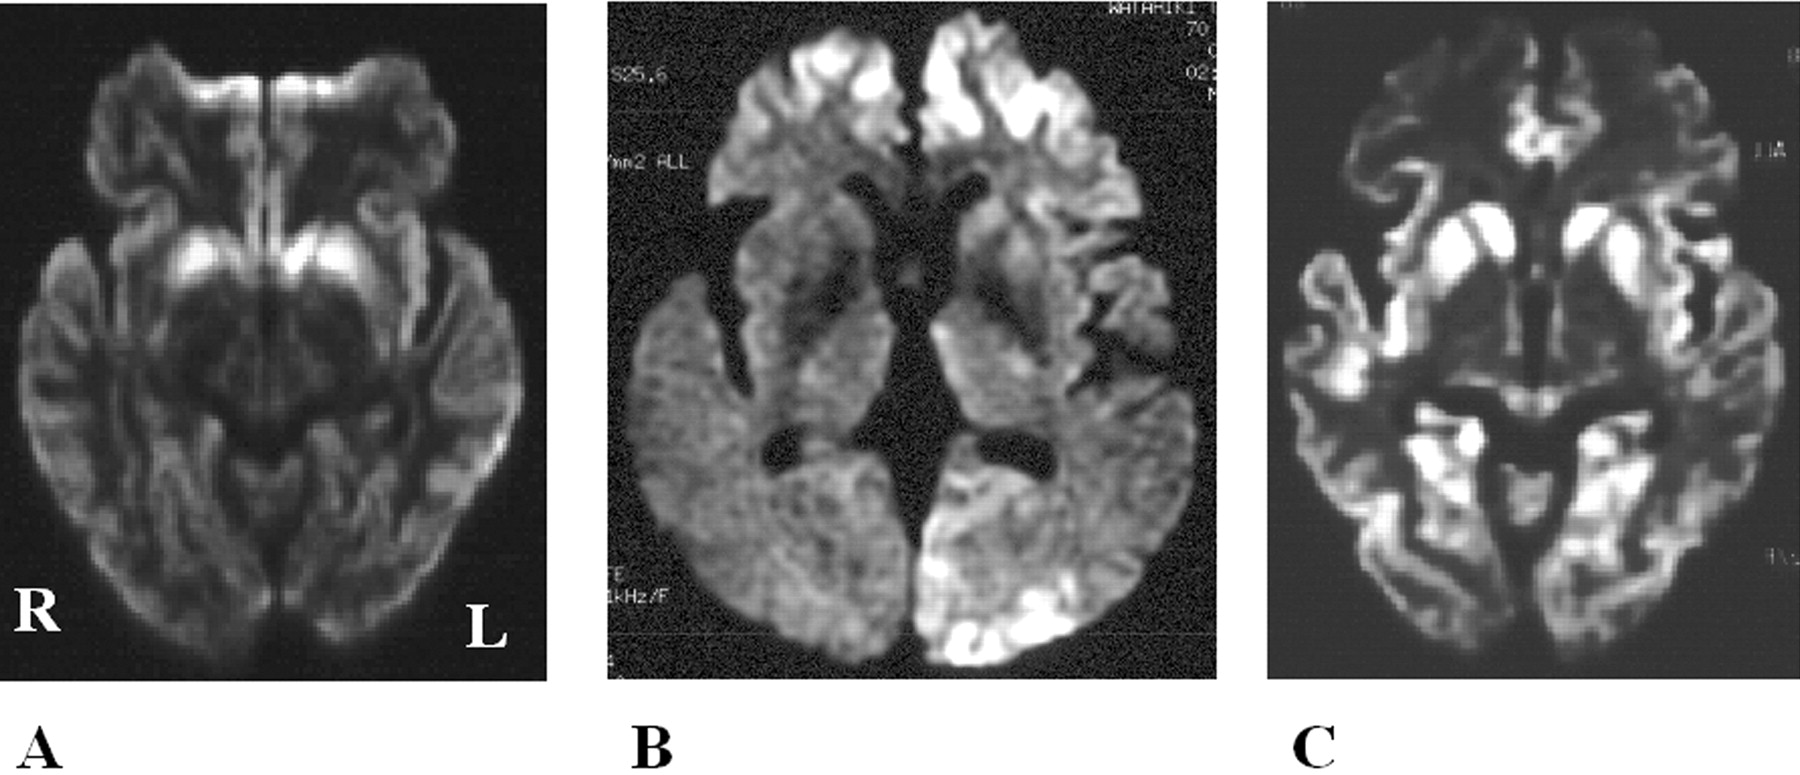

酒后驾驶是在26日检查库贾氏症患者发病后3到25周平均持续时间为10.7周。24库贾氏症患者表现出高强度脑损伤的驾车考试。两个观察者,醉酒驾车的库贾氏症诊断的敏感性为92.3%。interobserver协议率为100%。3例(12.5%)显示只在尾状头和硬膜损伤,10例(41.7%)患者显示线性损伤只有在大脑皮层,和11例(45.8%)患者显示病变基底神经节和大脑皮层(图1)。其中,只有三个病人(12.5%)显示,丘脑病变。没有病人显示高强度在小脑病变。高强度损伤在驾车之前出现脑萎缩。病变包括纹状体初并不总是对称的但是后来对称(图2),尽管对称的纹状体病变是众所周知的在库贾氏症。11在某些情况下,高强度损伤与连续驾车并不总是进展的疾病,而有时信号强度降低了疾病进展的一些病变。在某些情况下,皮质高信号强度不同,解剖分布(图3)。在终端阶段与深刻的脑萎缩,高强度损伤变得不清楚。T2I DWI-examined 26日在23日检查病人,但T2I扫描被排除在外,因为低质量由于运动构件。一位观察家认为11 22患者阳性(50.0%),而另一个观察者认为8阳性(36.4%)。interobserver协议率为68.2%,低于酒后驾车(p< 0.005)。在这两个观察者,醉酒驾车是比T2I更敏感(p一个观察者,< 0.005p另一个观察者p < 0.0005)。天赋是17 26患者的检查。一位观察家认为10 17例阳性(58.8%),和另一个观察者认为7是积极的(41.2%)。interobserver协议率为82.4%,也低于酒后驾车(p< 0.05)。醉酒驾车是比天赋更敏感(p一个观察者,< 0.01p另一个观察者p < 0.0005)。我们在图4一个例子中,只有醉酒驾车可以检测高强度异常病变。

图4。比较显眼的克雅氏病疾病变化相同的病人在不同的核磁共振序列。t2加权成像(A)和fluid-attenuated反转恢复成像(B)显示正常的结果,和diffusion-weighted MRI (C)展示了高强度在大脑皮层病变。